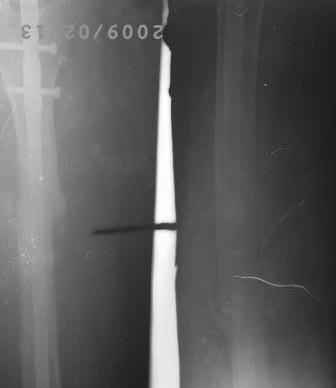

12.02.09г б-ная оперирована: з/остеоклазия (без особого труда- видимо тугой ложный сустав) коррекция деформации, удаление штифта из надвертельной обл, рассверливание канала гибкими развертками, реостеосинтез блокируюшим гвоздем Д-11мм.

P.S. Снимки не качественные, извиняюсь! последний снимок ЭРГА, два снимка объединил.

Я заранее приношу свои извинения, но по демонстрации видно, что сама методика БИОС использована с нарушениями. Да я с Вами согласен и сам часто встречался подобными случаями, когда из-за отсутствия функции конечности (опорной и двигательной) поврежденный сегмент теряеть минеральную плотность, тем самым развивается остеопороз. Однако Вам надо было заранее учитывать эти моменты и дистальные винты надо было установить четко бикортикально, в Вашем случае верхний дистальный винт короткий, нижний дистальный винт вне отверстия, в таком расположении он никак не может быть в блокирующем отверстии. Ранняя опорная нагрузка зависит от стабильности синтеза, веса пациента, но в любом случае дозированная нагрузка (собственный вес конечности) нужна, иначе срастить ложный сустав и ликвидровать остеопороз невозможно (кость должна выполнять свою функцию). С уважением Ерсин Жунусов.

Гвозди мы закупали из предприятия ЦИТО, и если Вы заметили у них нижнее дистальное отверстие продолговато-овальное, а не круглое, поэтому оно позволяет ввести винт и под углом, конечно это тоже ошибка, ну два последних винта было введено из одного маленького разреза - поэтому так получилось!